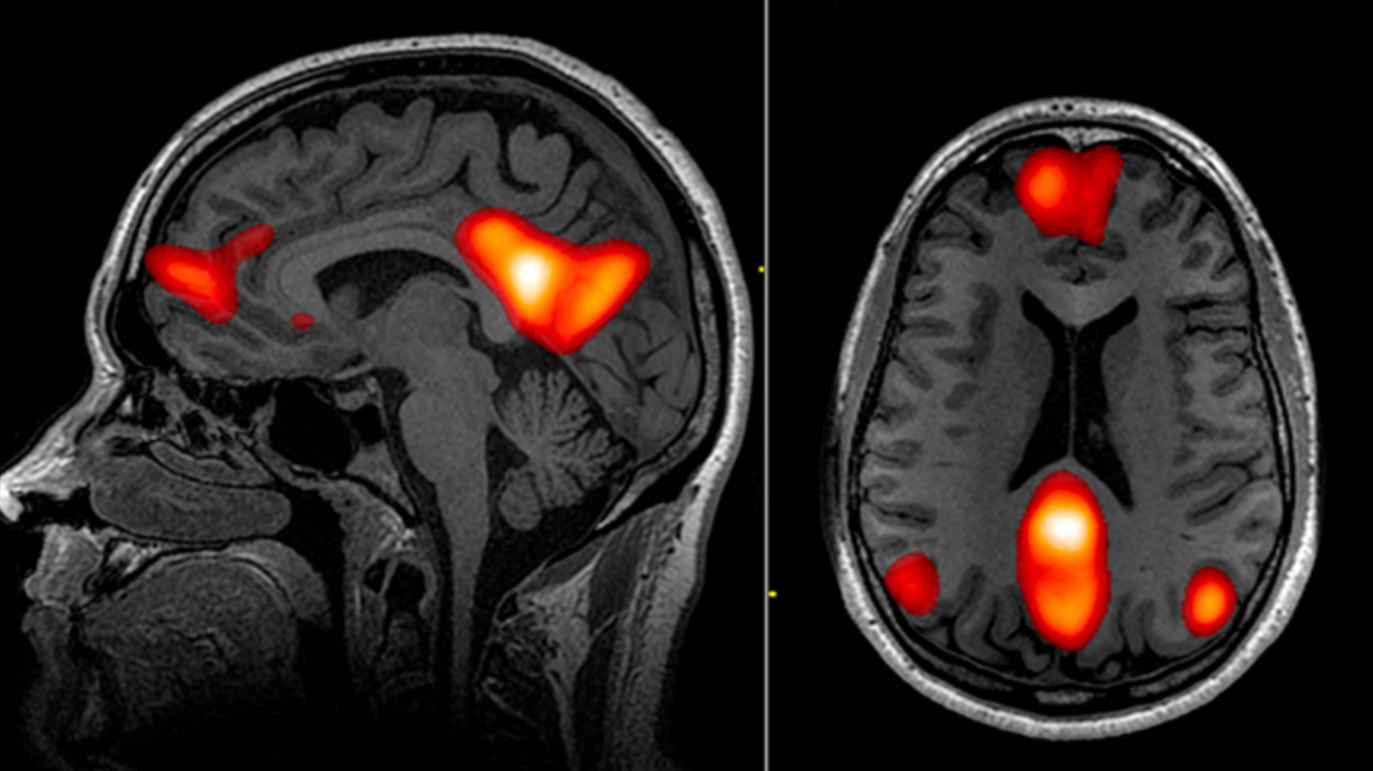

또한 fMRI(기능성 자기공명영상) 연구를 통해

‘디폴트 모드 네트워크(Default Mode Network, DMN)’가

이 시기에 특히 활성화된다는 사실도 밝혀졌습니다.

DMN은 우리가 아무 일도 하지 않을 때, 즉 ‘멍 때릴 때’ 작동하는 뇌 네트워크로,

기억, 상상, 자기반성 등을 담당합니다.

즉, 겉으론 쉬고 있지만 뇌는 연결을 계속 확장하고 있는 것이죠.